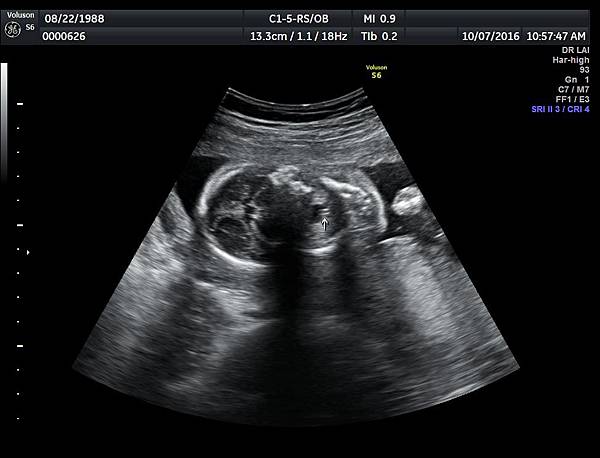

一個檢查如果要花很長的時間才能完成,這樣的檢查無法變成常規的篩檢方式,我已經在我的診所執行懸雍垂檢查一段時間,我檢查懸雍垂大約30 秒,前提是胎兒的臉最佳位置是側躺,其次是側躺偏向上,我的檢查步驟是上顎(含日後大門牙長出的位置)、舌頭、懸雍垂(= equal sign)(附圖1~8),如果超過60秒無法完成,只有兩個原因,一個是胎兒姿勢不適合或喉嚨羊水空間太小,這時候不要硬碰硬,只要先檢查其他部位,等待時機再回來即可,我的經驗是90%的cases都能順利完成這項檢查(肚皮厚的case真的是很難)。

有興趣的同業可以參考我的部落格備忘錄第119、120、127 及 236 這四篇,裡面有我做懸雍垂(uvula)的相關影像。